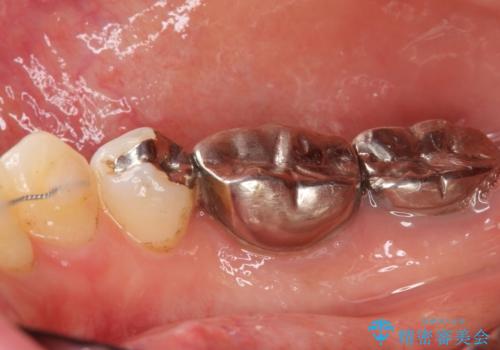

低予算で銀歯を白くしたい 50代女性

- 低予算で銀歯を白くしたいとご希望し来院された患者様です。

右上小臼歯(右上5)はオールセラミッククラウン(e-max press)、下顎臼歯(下顎両側67)はメタルボンドクラウンによりやりかえることにしました。

~クラウンの種類~

右上小臼歯(右上5):オールセラミッククラウン エコノミー

下顎両側臼歯(下顎両側67):メタルボンドクラウン エコノミー